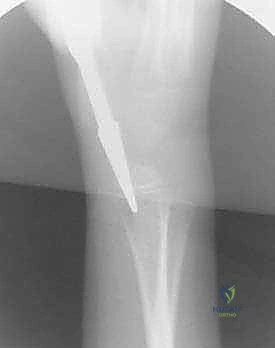

تُعد تقنية التثبيت بالمسامير المرنة داخل النخاع (Flexible Intramedullary Nailing - FIN) أو مسامير التيتانيوم المرنة (Titanium Elastic Nails - TENs) المعيار الذهبي (Gold Standard) لعلاج كسور الساعد غير المستقرة لدى الأطفال. والأستاذ الدكتور محمد هطيف هو رائد هذه التقنية في اليمن.

يتم إدخال مسمارين مرنين (عادة من التيتانيوم أو الصلب الطبي المقاوم للصدأ) داخل التجويف النخاعي (Marrow Canal) للعظم. يتم ثني هذه المسامير مسبقاً بواسطة الجراح لتشكيل قوس. عندما يتم إدخالها في العظم، فإنها تعمل بمبدأ "التثبيت ثلاثي النقاط" (Three-Point Fixation). تولد المسامير المرنة قوة شد داخلية تدفع أجزاء العظم المكسور نحو بعضها البعض، مما يوفر استقراراً حيوياً ميكانيكياً (Biomechanically Stable) يسمح بتكوين الكالس (Callus) وشفاء العظم بسرعة فائقة.

الدليل الجراحي التفصيلي: خطوة بخطوة مع الأستاذ الدكتور محمد هطيف

لإبراز المستوى المتقدم من الرعاية الطبية، نستعرض هنا الخطوات الدقيقة التي يتبعها الأستاذ الدكتور محمد هطيف وفريقه الجراحي في غرفة العمليات المجهزة بأحدث التقنيات.

1. التخطيط قبل الجراحة واختيار المسامير

قبل بدء العملية، يقوم الدكتور هطيف بدراسة الأشعة السينية بعناية لتحديد قطر المسامير المناسب. القاعدة الذهبية هي أن يملأ المسماران معاً حوالي 80% من أضيق نقطة في التجويف النخاعي. يتم ثني المسامير مسبقاً لتحقيق أقصى قدر من الاستقرار.

5. إدخال المسمار المرن

يتم إدخال المسمار المرن (المثني مسبقاً)